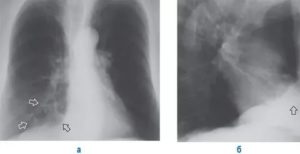

Визуально после пневмонии он определяется на рентгеновских снимках в виде фиброзных тяжей и рубцов – полосы затемнения. Это приводит к уменьшению дыхательной поверхности легких и развитию хронической дыхательной недостаточности.

Фиброзные тяжи на рентгеновском снимке

По результатом обследований наблюдаются фиброзные очаги (тяжи, рубцы) и значительное снижение функции легких.